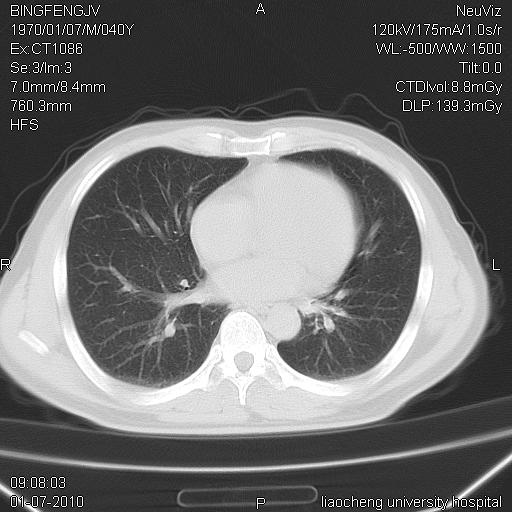

标题: CT23764B:男 40 肺部CT [打印本页]

标题: CT23764B:男 40 肺部CT

治疗2周后

考虑左肺上叶近胸膜下炎症并肺气囊形成。

炎症,大部吸收。